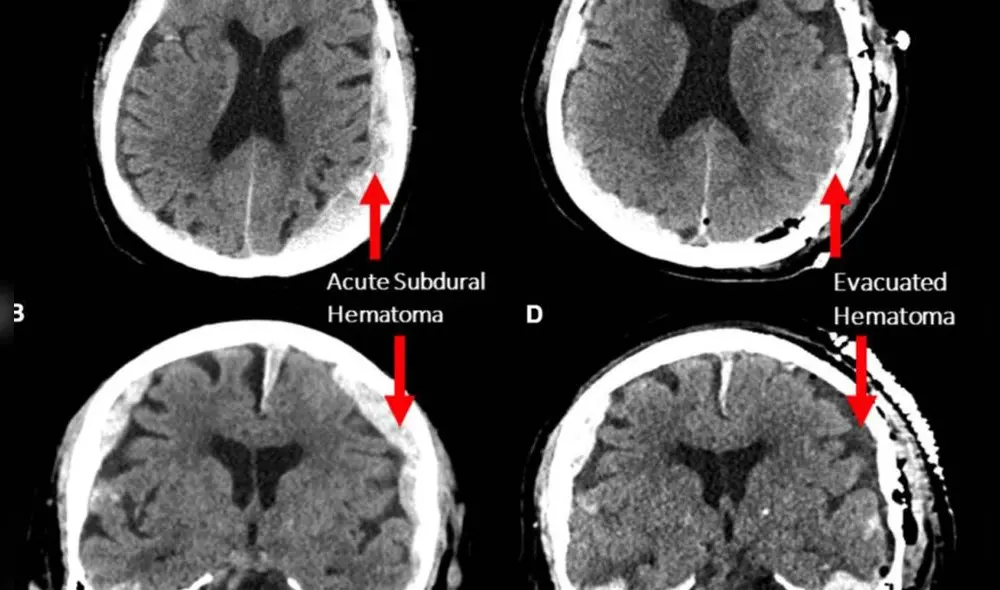

De acuerdo con el reporte, el hallazgo se realizó de forma accidental en un paciente de 87 años en Estonia. El hombre había sufrido una caída y fue diagnosticado con una hemorragia cerebral significativa. Posteriormente, lo operaron exitosamente y se mantuvo estable durante dos días en cuidados intensivos.